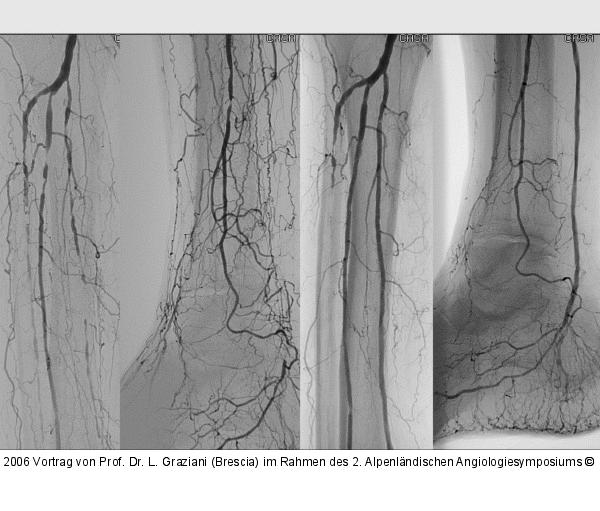

PTA of the foot arteries in diabetics: Extremities Extreme Angioplasty

Abbildung 24: Revaskularisation